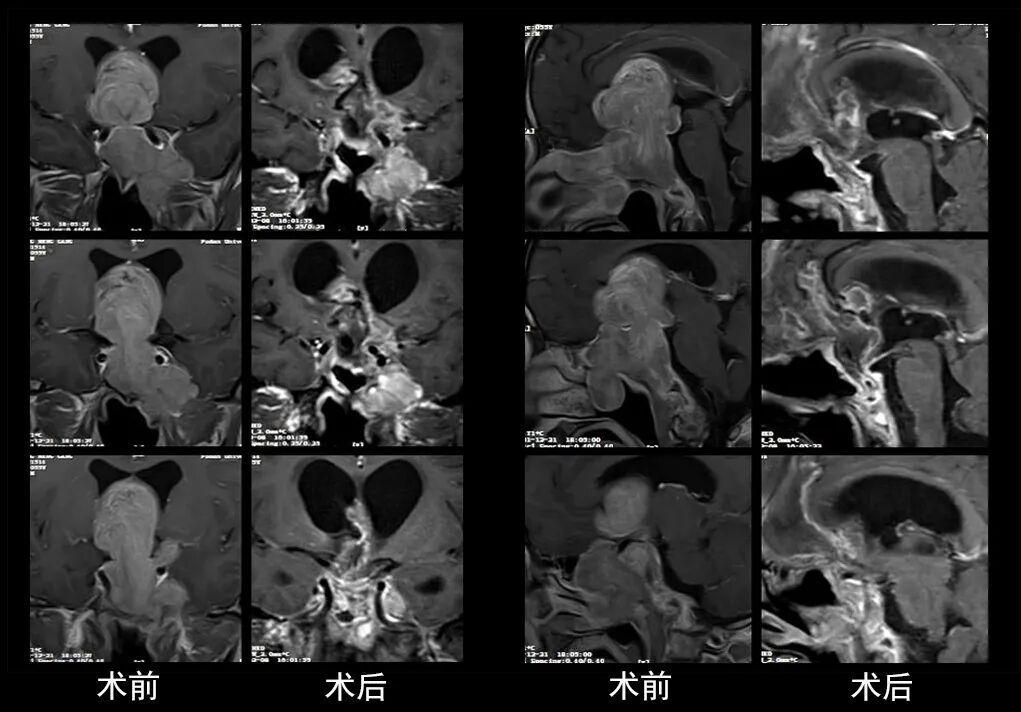

本研究中采用联合手术策略的代表性病例展示:

左右滑动查看更多

图片

case 7

case 8